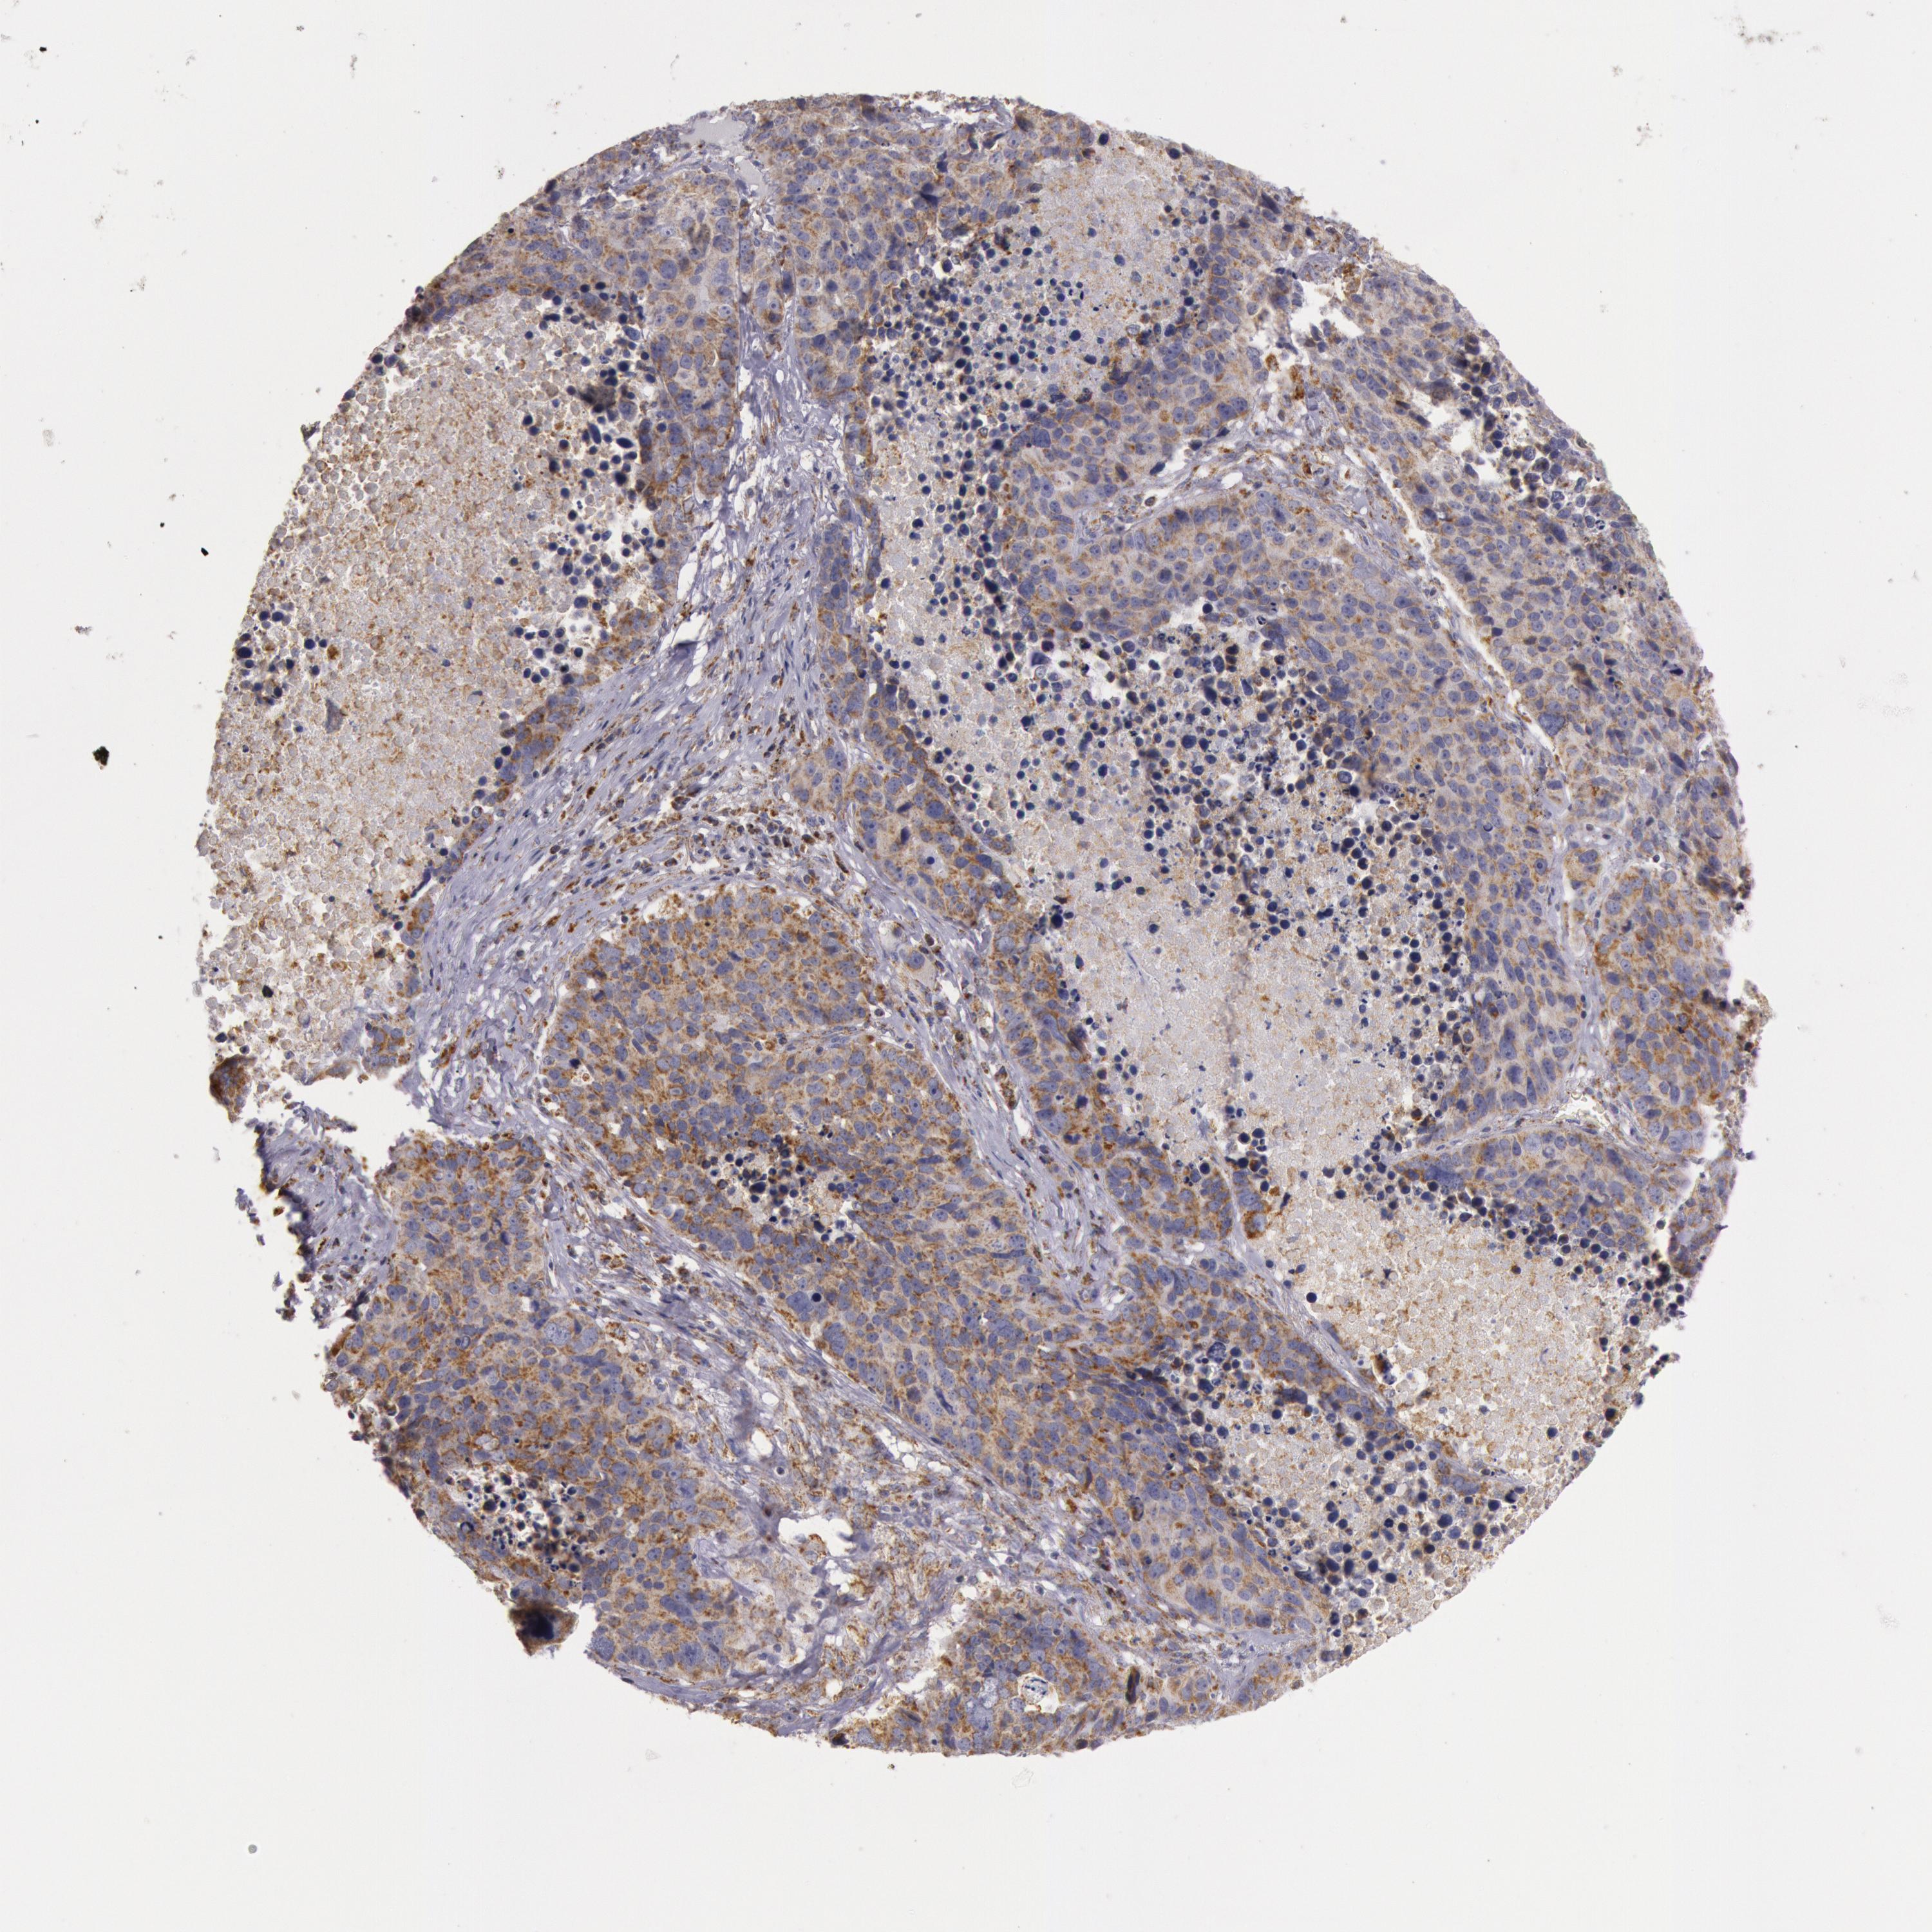

CANCER LUNG CANCER Show tissue menu

LUAD TCGA LUAD VALIDATION LUSC TCGA LUSC VALIDATION PROTEIN LUAD CPTAC PROTEIN LUSC CPTAC PROTEIN EXPRESSION

ANTIBODIES

AND

VALIDATION